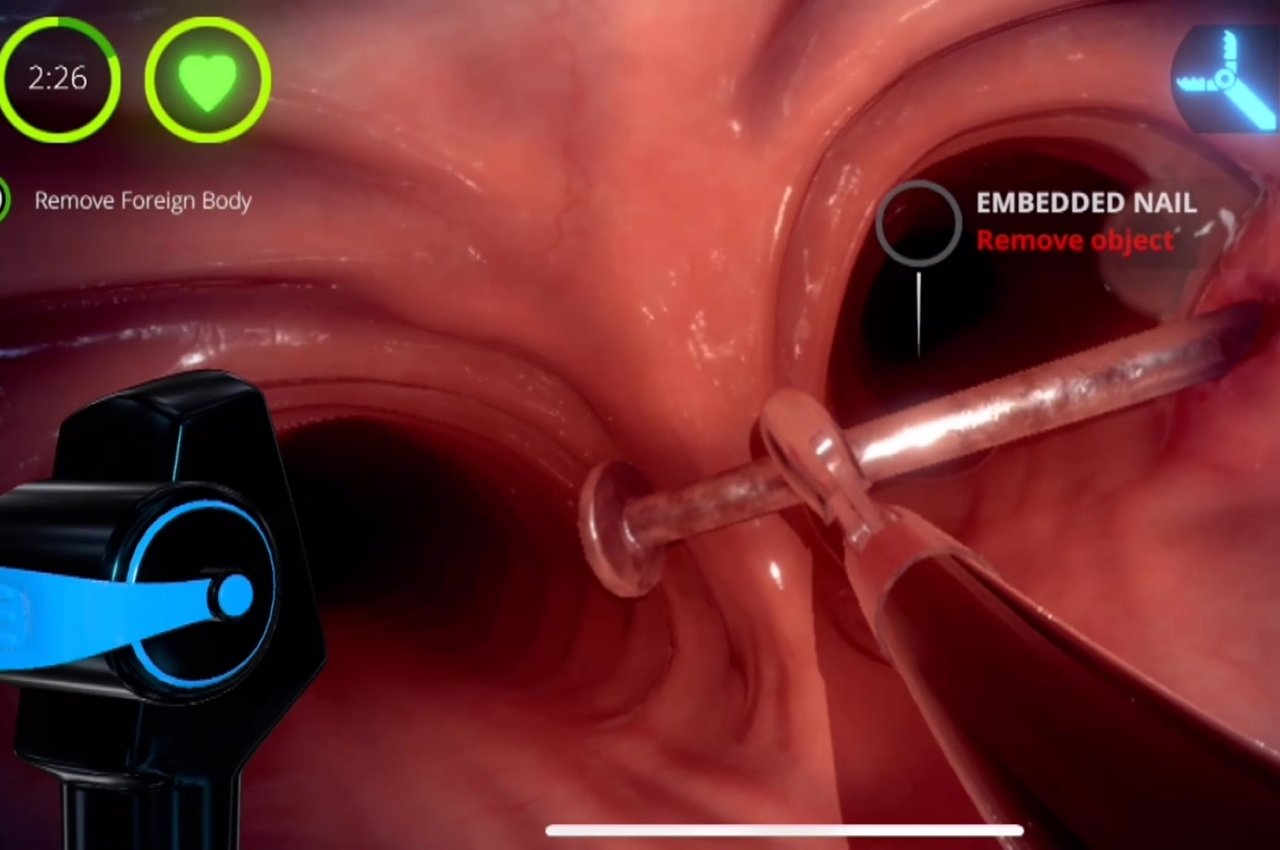

Il Metaverse riguarda il divertimento e i giochi non è necessariamente una cosa negativa, specialmente se fatto con moderazione. In effetti, giocare non è una brutta cosa, nonostante le connotazioni e i pregiudizi che circondano anche solo la parola. Le persone hanno imparato molto tempo fa che i giochi, o in particolare le attività ludiche, possono essere utili per l'apprendimento e l'adattamento a cose nuove. Può anche aiutare le persone a far fronte a traumi o stress.

La gamification, o l'applicazione del pensiero di gioco e delle meccaniche di gioco ad attività non di gioco, esiste ormai da anni. Dalle classifiche ai livelli ai punteggi più alti, queste piccole cose possono dare un senso di realizzazione che rafforza le nuove conoscenze che abbiamo appena acquisito. E poiché le stesse tecnologie utilizzate per creare giochi creano anche il Metaverse, l'intersezione tra la ludicizzazione e il Metaverse è praticamente nella borsa.

Nasa, ad esempio, ha arruolato uno sviluppatore di giochi specializzato nell'utilizzo di giochi per formare persone, in particolare medici, nella diagnosi e nel trattamento di diverse condizioni. L'idea è quella di addestrare gli astronauti ad avere sufficienti conoscenze mediche in caso di emergenza, nel caso in cui sia il medico di bordo che necessita di cure. Questi strumenti educativi hanno tutti i tratti distintivi dei tipici giochi per dispositivi mobili, tranne per il fatto che ti allena con abilità serie e salvavita piuttosto che semplicemente schiacciare lo schermo per ottenere uccisioni.

Progettista: Livello Es